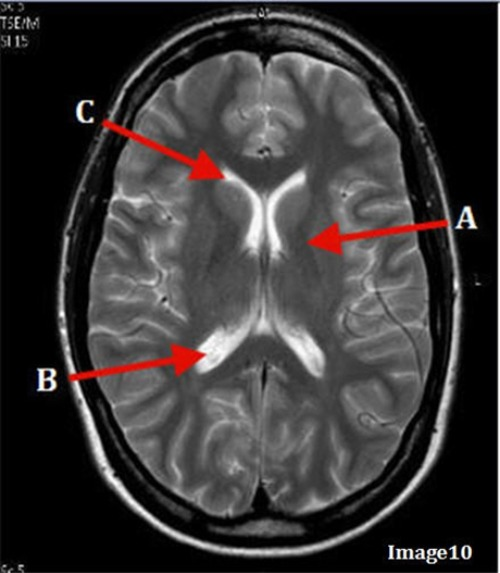

Letter C in Image 10 is pointing to:

C. Anterior horn lateral ventricle

Letter B in Image 10 is pointing to:

D. Posterior horn lateral ventricle

Letter A in Image 10 is pointing to:

B. Basal ganglia